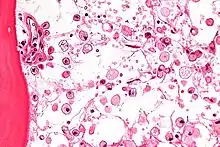

| Micrograph of Gaucher disease, with cells that have the characteristic crumpled tissue paper-like cytoplasm. H&E stain. | |